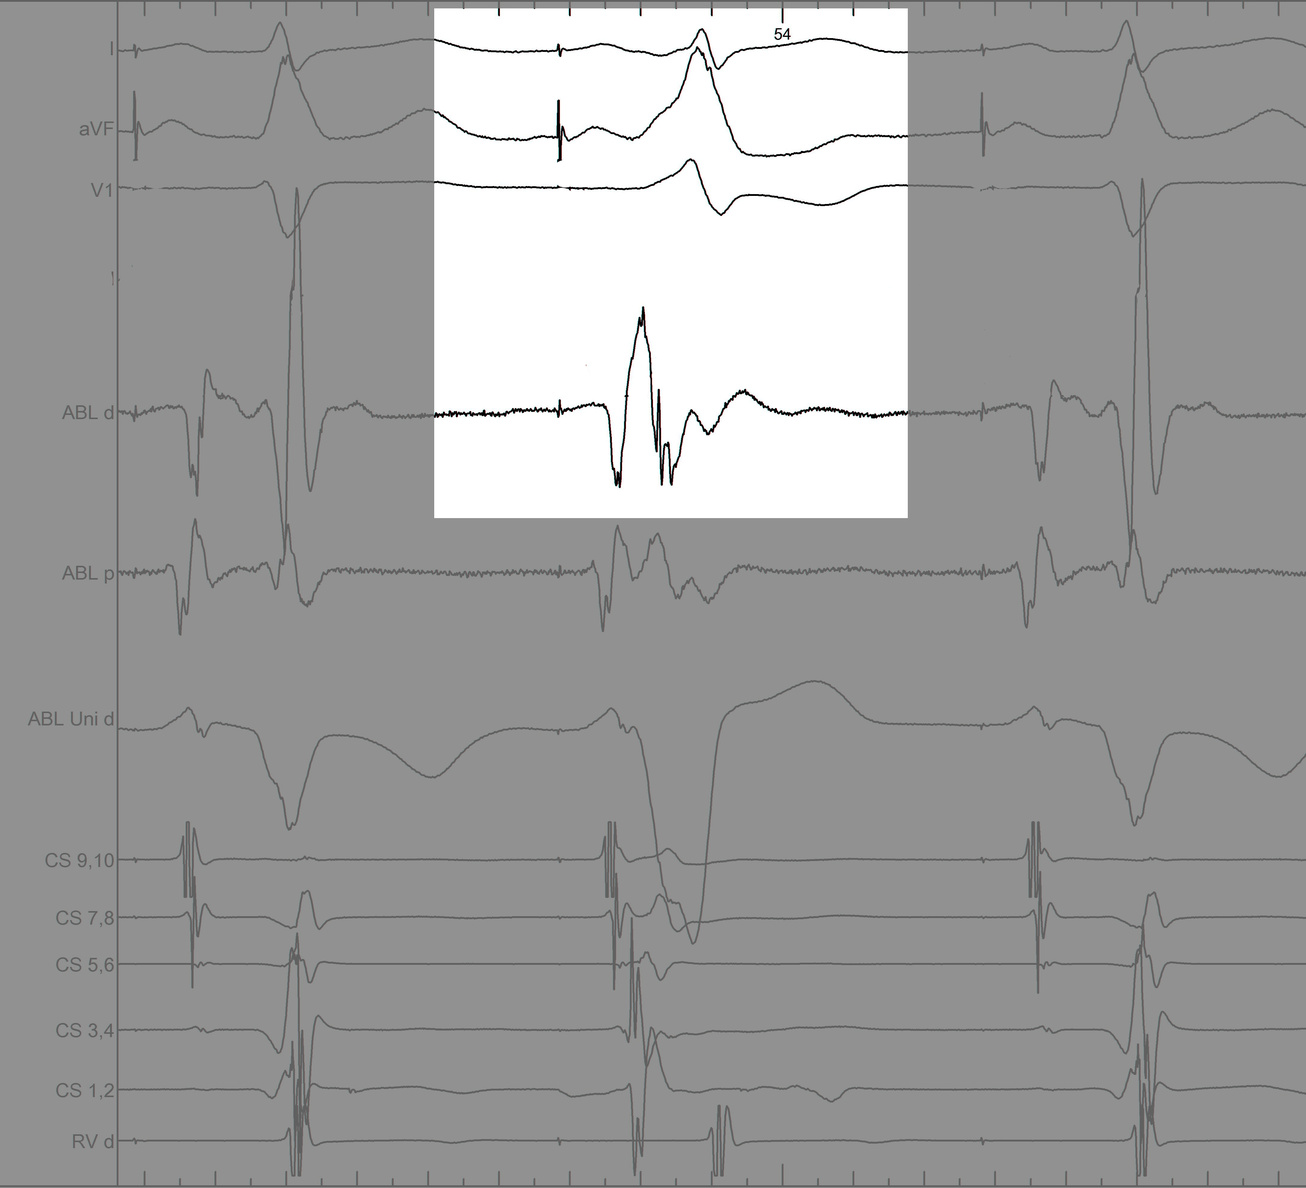

#4 Key to mapping is to identify signal components

pseudo_disappearance.jpg